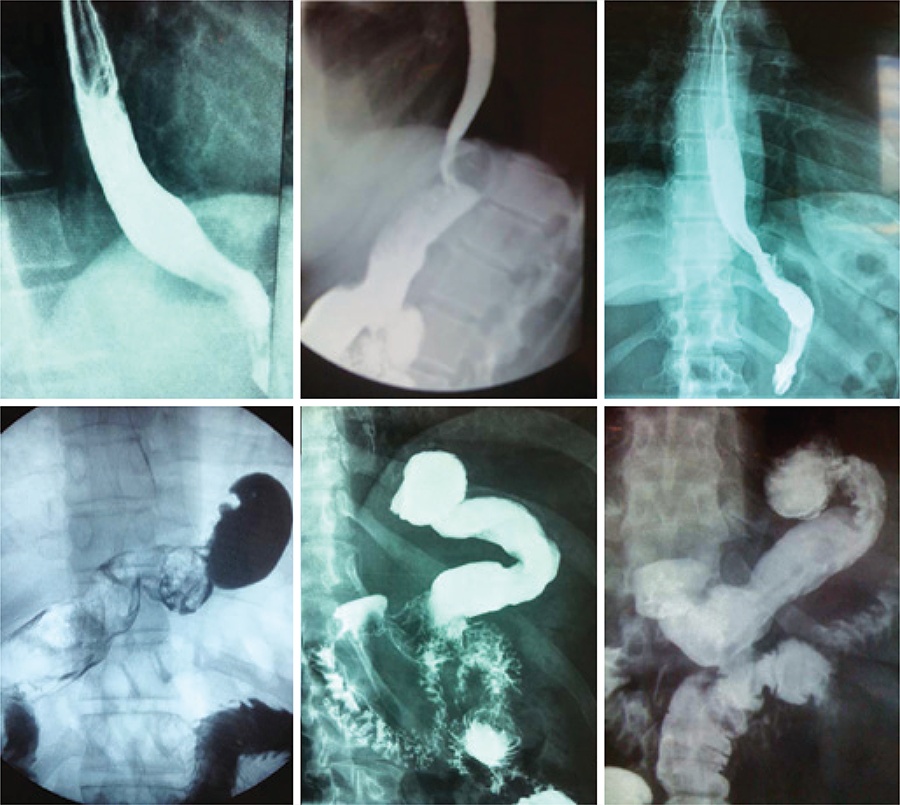

A gastrectomia vertical é o procedimento cirúrgico para tratamento da obesidade que mais cresce em indicações. No entanto, esse procedimento pode causar ou agravar a doença do refluxo gastresofágico. Este artigo buscou descrever originalmente a adição de procedimentos antirrefluxo (remoção de coxins gordurosos do hiato, hiatoplastia, pequena plicatura e fixação do remanescente na posição anatômica), além de relatar seus resultados precoces e tardios.

Foram submetidos à gastrectomia vertical com medidas antirrefluxo 88 oito pacientes obesos com sintomas de doença do refluxo gastresofágico. Dentre esses pacientes, 50 foram submetidos também à bipartição do trânsito. A perda de peso destes foi comparada àquela ocorrida em 360 pacientes consecutivos submetidos à gastrectomia vertical usual e à de 1.140 pacientes submetidos à gastrectomia vertical + bipartição do trânsito. Os sintomas do refluxo gastresofágico foram investigados por meio de questionário em todos os submetidos à gastrectomia vertical com medidas antirrefluxo e comparados com os resultados obtidos em 50 pacientes submetidos à gastrectomia vertical usual e a 60 submetidos à gastrectomia vertical + bipartição do trânsito, também com sintomas prévios de doença do refluxo gastresofágico.

O percentual de perda do excesso de índice de massa corporal após gastrectomia vertical antirefluxo não foi inferior a gastrectomia vertical usual. Além disso, a gastrectomia vertical antirefluxo + bipartição do trânsito não foi inferior a gastrectomia vertical + bipartição do trânsito. Não houve aumento da morbidade na gastrectomia vertical antirefluxo, porém notou-se redução significativa dos sintomas da doença e do uso de inibidores de bomba prótons para tratar a condição.

A adição de procedimentos antirrefluxo, como a hiatoplastia e a cardioplicatura, à gastrectomia vertical usual não acrescentou morbidade nem piorou a perda de peso obtida, mas diminuiu de modo significativo a ocorrência de sintomas da doença do refluxo no pós-operatório, assim como a utilização de inibidores de bomba de prótons.